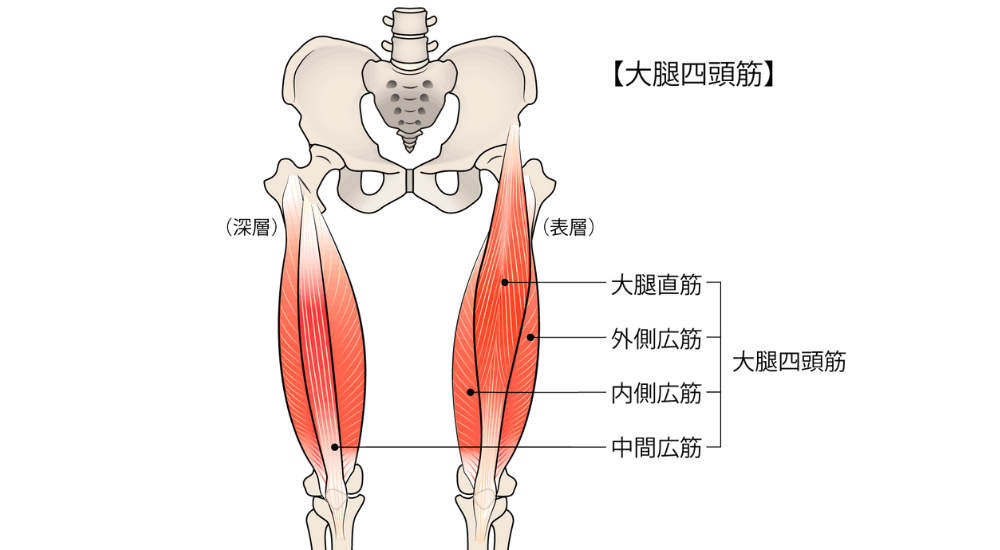

- 大腿四頭筋:

太ももの前側の筋肉です。骨盤の傾きに関与し、硬くなると反り腰になり、腰に負担をかけます。